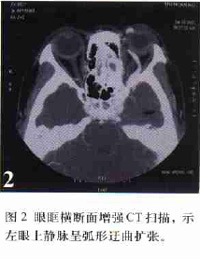

頸內動脈海綿竇瘺CCF的診斷主要是靠其典型的臨床表現及典型的眼征,尤其是加上有顱腦外傷史即可確定診斷。頭顱CT、MR可發現突眼,海綿竇顯影增強或眼靜脈增粗,可作為輔助診斷。

患者,男,31歲,因車禍致頭痛並右側 鼻腔流血水3h入院。診斷為雙側額葉腦挫傷、 顱底骨折。給予 神經外科常規治療, 鼻腔漏液顏色逐漸變淡,且時斷時續。入院後第13天右側 鼻腔突然出現暴發性 鼻出血,請耳鼻喉科給予右側後鼻腔填塞,止血效果滿意。第15 天行全腦血管 造影確診為右側頸內動脈海綿竇瘺合併右側頸內動脈、眼動脈瘤。經對症處理,作好Mata訓練後於第18 天行介入治療。穿刺右側股動脈置5F鞘,行全腦血管 造影示右側頸內動脈海綿竇瘺,右側頸內動脈眼動脈瘤。穿刺左側股動脈置8F鞘,置8F導引導管於右側頸內動脈,經導引導管置不可脫 球囊閉塞右側頸內動脈,同時行左側頸內 動脈造影,示右側 大腦半球側支循環良好。經 造影管置5cm×8mm 彈簧圈於右側頸內及頸外動脈起始處,計10枚,造影示血流減少,緩慢。拔除雙側股動脈鞘,加壓包紮。